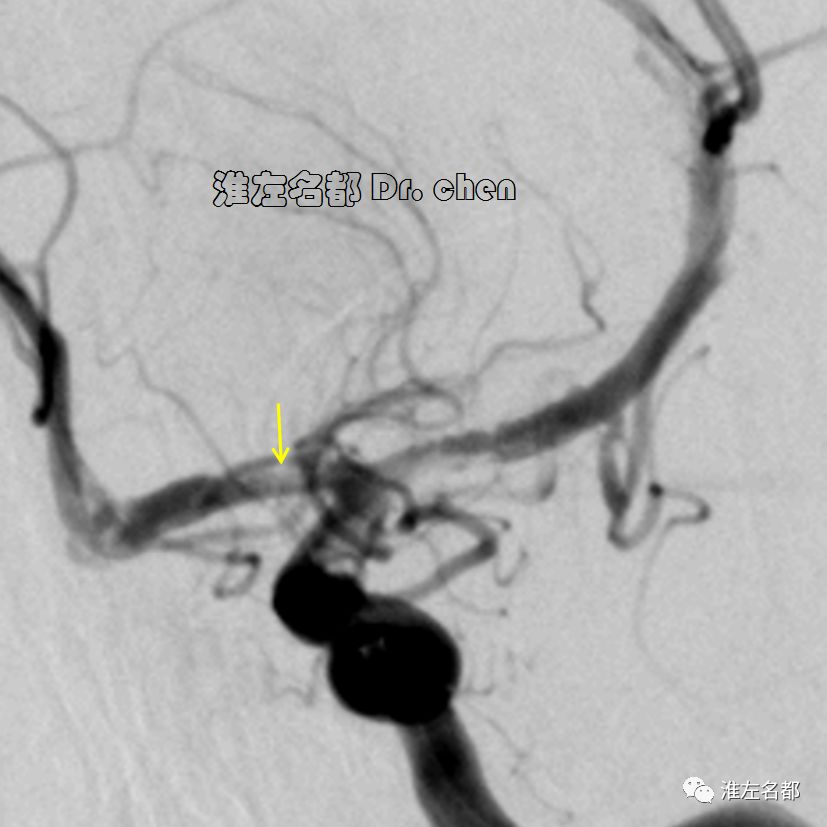

△管壁高分辨MRI(增强T1-SPACE):左侧颈内动脉末端检测到夹层“内膜征”(橙箭)。

3.脑动脉夹层临床确诊依赖于影像学检测到典型夹层征象:内膜征/双腔征、长段不规则/丝线样狭窄、壁内血肿、夹层动脉瘤等。本患儿DSA显示左侧颈内动脉末端和大脑中动脉主干长段狭窄,且大脑中动脉主干狭窄呈“丝线样”,符合夹层影像学征象。

6.在夹层真腔得以基本恢复后,DSA于左侧颈内动脉末端、大脑前和中动脉近端均检测到典型“内膜征”,进一步确定了夹层诊断。